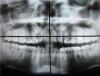

Orlando Опубликовано 18 октября, 2009 Поделиться Опубликовано 18 октября, 2009 Очень нужна консультация ортодонта. Мне 25 лет. Решила поставить брекеты. Была у одного ортодонта. Говорит, что вытянуть клыки не получится, нужно удалять. Еще нужно удалить 4-ки вверху и внизу. Удалять клыки не хочется, т.к. пугают тем, что при операции могут задеть гайморовы пазухи. Может все-таки попробовать вытянуть? Завтра иду на консультацию к хирургу, потом к другому ортодонту. Без удаления и без вытягивания нет смысла ставить брекеты для выравнивания передних зубов, т.к. клыки на них сверху давят (так ортодонт сказала). Что в моем случае можно сделать? Посоветуйте, пожалуйста. http://i081.radikal.ru/0910/44/a3908c4d7d39.jpghttp://i008.radikal.ru/0910/45/230181ad7100.jpghttp://i057.radikal.ru/0910/b4/8df5ded78c7c.jpghttp://s51.radikal.ru/i133/0910/61/1b9bfe4cea94.jpghttp://s55.radikal.ru/i148/0910/21/a2fed151a040.jpghttp://s39.radikal.ru/i084/0910/df/e90d8ad8a7fb.jpg Снимок сделан неделю назад. Раньше снимков не делала. Последний молочный клык удалили в 13 лет, сам не выпадал и был в нормальном состоянии. Ссылка на комментарий

krasik Опубликовано 18 октября, 2009 Поделиться Опубликовано 18 октября, 2009 По снимку эти "клыки" больше похожи на четвертые зубы. Ссылка на комментарий

krasik Опубликовано 19 октября, 2009 Поделиться Опубликовано 19 октября, 2009 Как четвертые? У меня же есть 4-ки. Или бывает по два комплекта четверок????Бывает и так, что у каких то зубов есть "двойники". На представленном снимке зубы, которые в челюсти, очень не похожи на клыки и очень похожи на четвертые или пятые зубы верхней челюсти. Ссылка на комментарий

Премоляр Опубликовано 19 октября, 2009 Поделиться Опубликовано 19 октября, 2009 Ну судя по наклону двоек клыки расположены вестибулярно. Советую вам обратиться на конс. к другому ортодонту с целью выяснения альтернативного плана лечения(если такой будет).Это не значит что ваш врач некомпетентен.Просто сравните еще одно мнение. КТ необходима!!! Для решения вопроса о удалении или сохранении и вытяжении клыков,степени резорбции корней двоек и т.д... В любом случае-необходимо ортодонт.лечение-независимо от удалений.Наклоны зубов не функциональны..да и промежутки тоже неэстетичны Ссылка на комментарий